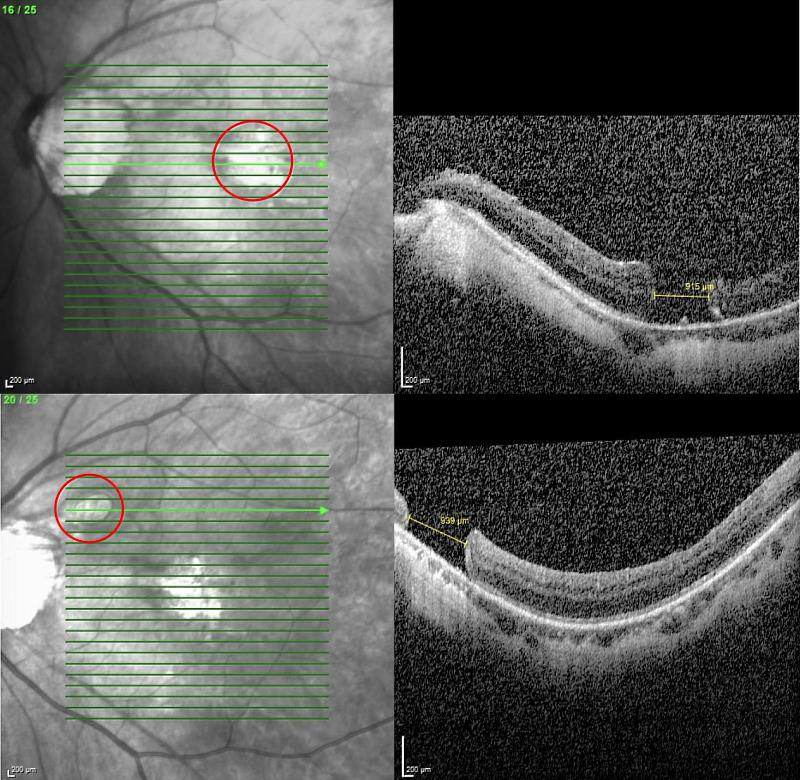

何明山主任在仔細檢查發現,張女士左眼同時有兩處大型黃斑部裂孔,分別為915與939微米,屬於少見的雙裂孔個案。何明山主任表示,得知張女士從過去一例成功治癒巨大黃斑部裂孔的報導中抱著希望,專程來到花蓮就診,針對此特殊情況,何明山主任採用創新雙重療法,以羊膜移植修補破洞,並輔以自體高濃度血小板血漿(platelet-rich plasma, PRP)注射,促進組織修復與裂孔癒合。